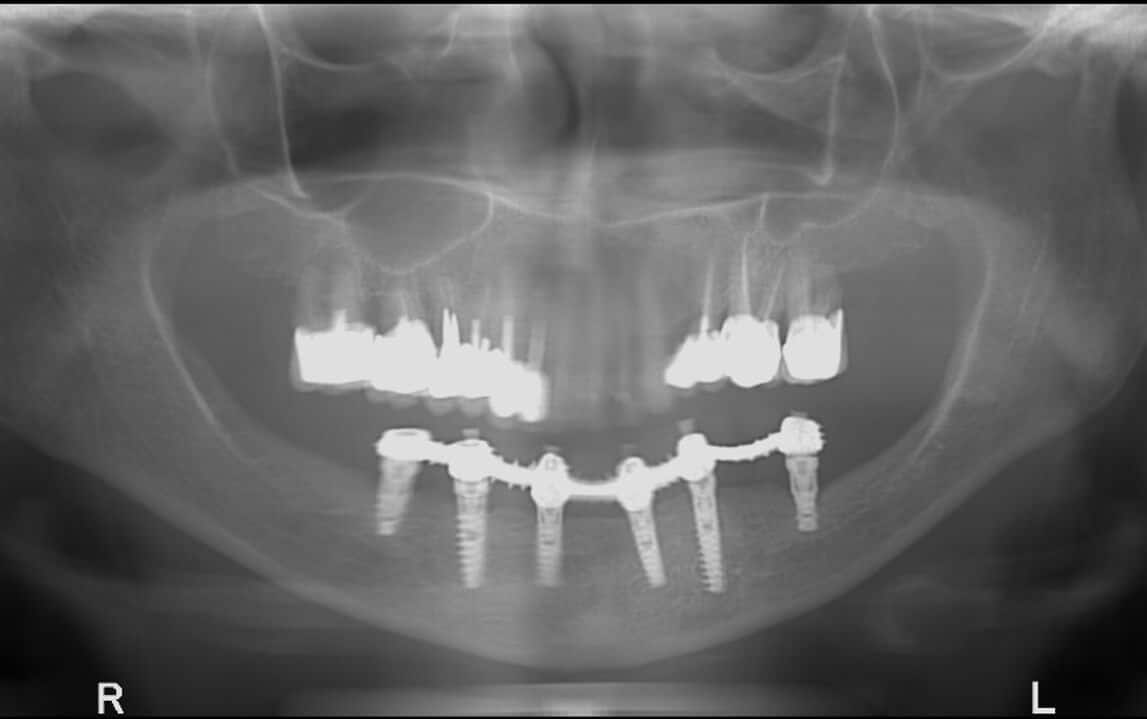

Доктор Балан считается одним из ведущих стоматологов мира.

Широкие профессиональные знания и обширный практический опыт, накопленный за 25 лет работы в клинике,

позволяют предлагать нашим пациентам уникальные решения для реабилитации челюстей и выполнения качественных имплантаций даже в сложных случаях нехватки костной массы или в случае пациентов,

которые испытали несколько неудачных лечений в прошлом.

Процесс установки зубного имплантата